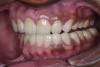

Figure 2. Preoperative 1:2 retracted frontal view.

Figure 2

A thorough clinical examination and analysis were carried out to assess the esthetic and functional problems of the patient (Figure 2 through Figure 7). The medical history was non-contributory, except for mild leukoderma. Temporomandibular joint (TMJ) function was within normal range.